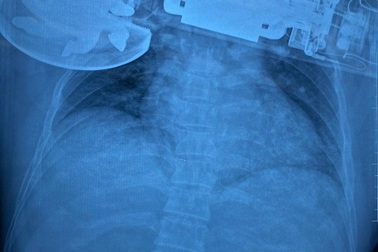

Người đàn ông bị dây kẽm dài 20cm xuyên vào lồng ngựcNgày 2/2, Bệnh viện Đa khoa Trung ương Quảng Nam cho biết vừa cấp cứu, phẫu thuật thành công, cứu sống nam bệnh nhân bị dị vật kẽm có bọc nhựa dài 20cm xuyên vào lồng ngực.

Ngồi trong lớp đạn xuyên vào má, đi lễ chùa đạn găm trúng ngựcĐang chuẩn bị dâng lễ trong chùa, bà Lý bỗng thấy đau buốt vùng ngực, nhìn xuống bà thấy máu đang chảy liên tục. Sau khi được đưa đi cấp cứu, bà Lý kinh hoàng khi biết có một đầu đạn vừa xuyên vào nằm gọn trong ngực bà...

Vào viện cấp cứu, người đàn ông ôm theo máy chà cắm găm vào ngựcBệnh nhân vào viện với vết thương không chảy máu, chiếc máy chà vẫn cắm găm vào ngực. Phần mềm thành ngực bị cuốn vào máy chà gây khuyết da lớn, bầm dập da quanh tổn thương.

Cứu sống bệnh nhân bị dao găm dài hơn 11cm đâm thủng phổiCác bác sĩ Bệnh viện đa khoa tỉnh Bình Định đã tiến hành ca phẫu thuật, lấy lưỡi dao găm dài 112 mm ra khỏi phổi của bệnh nhân. Hiện, sức khỏe bệnh nhân đang bình phục tốt.